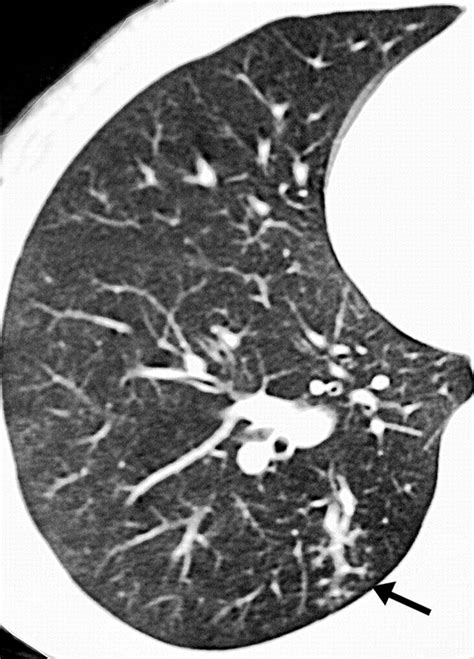

The tree in bud opacities appearance is fundamentally a reflection of airway pathology. On a CT scan, the "tree" component represents dilated, fluid-filled bronchioles (the smallest airways in the lung), while the "buds" represent the accumulation of mucus, pus, or fluid in the acini, which are the functional units of the lung located at the ends of these bronchioles. This pattern typically suggests that something is causing inflammation, infection, or obstruction within the small airways.

Because these opacities are located in the periphery of the lungs, they are easily distinguished from larger airway diseases. Radiologists look for these clusters of small nodules that connect to a branching structure. When you see this term on your report, it indicates that the air spaces are being filled with abnormal material, effectively "plugging" them and creating the characteristic visual pattern.